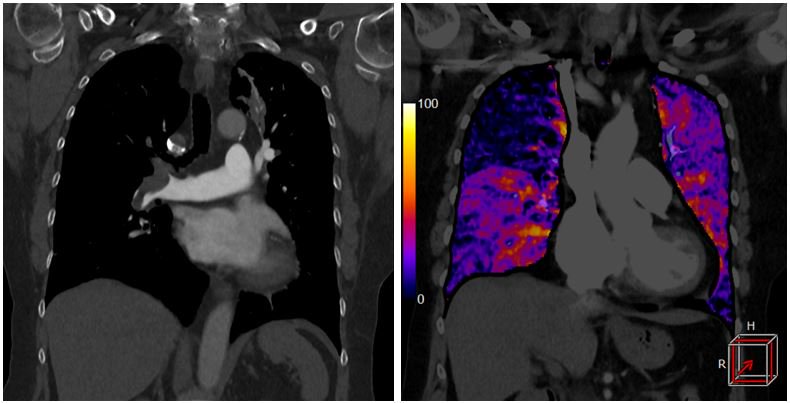

Автоматична субтракція для отримання йодної карти легень – SURESubtraction Lung*

Дозволяє визначити розподіл накопичення йоду в паренхімі легенів для оцінки периферичного дефекту контрастування при хронічній ТЕЛА. Легенева КTA є широко розповсюдженим обстеженням для оцінки пацієнтів з підозрою на легеневу емболію. Проте, виявлення невеликої або субсегментарної емболії може бути ускладнене або неможливе. Субтракція дає можливість створити йодну карту паренхіми легень з високим співвідношенням контрасту до шуму. Використання кодування кольором дозволяє легко визначити області гіпоперфузії в легенях, підвищуючи реальну діагностичну цінність у хворих з прихованою емболією.

Так як тромбоемболія легеневої артерії пов'язана зі значним ризиком для життя пацієнтів, прогноз залежить від правильно і вчасно поставленого діагнозу і лікування.